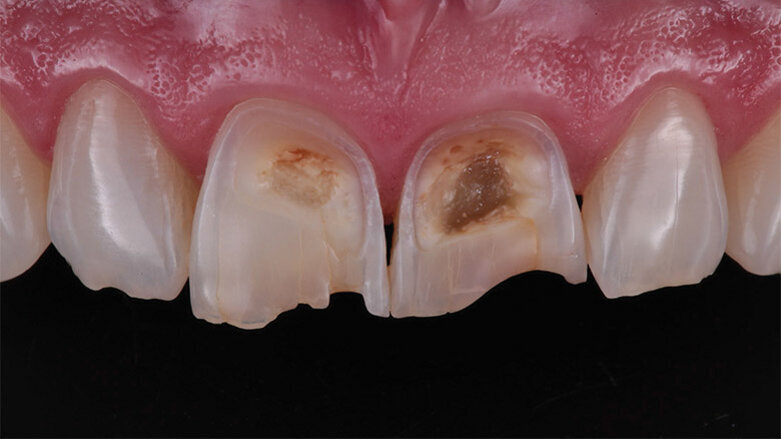

Detailed view of the maxillary incisors. The teeth didn’t show any highly translucent areas, so the use of a single shade/opacity of 3M™ Filtek™ Universal Restorative was selected.